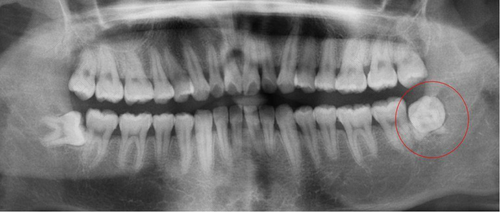

首先,成年人的牙齿已经长成,不会再有换牙的经历了,牙齿的问题也会伴随以后的生活了,如果出现的问题比较严重的话,可以在医生的指导下进行拔除。但是,智齿在口腔的最后方,拔除的话是需要拍一个口腔片的。

因为,智齿生长的位置比较特殊,深度也是比较大的,如果拔除的话,给人们带来的伤害也是比较严重的。如果有拔除需要的话,医生会建议拍片,看看是否有不适合拔除的问题。这样对身体造成的伤害会有所减少,人们不要存在侥幸心理。